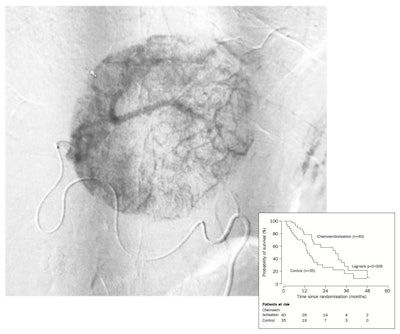

I'd like to leave you with the image above of a transarterial chemoembolization (TACE) procedure. The patient survived for 22 months from the time the image was taken. What will you remember most about her? Her angiogram or the Kaplan-Meier chart predicting her fate?